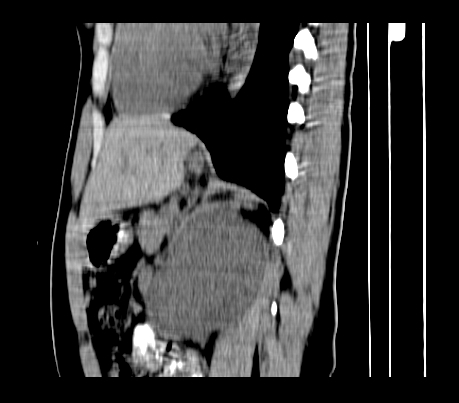

标题: CT23915:女 20岁 全身长疙瘩三年 今日多体位查 看看吧 [打印本页]

标题: CT23915:女 20岁 全身长疙瘩三年 今日多体位查 看看吧

静脉期

神经纤维瘤病

支持 神经纤维瘤病。